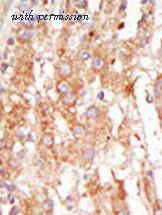

application: western blot, immunohistochemistry, immunohistochemistry - paraffin section - domestic rabbit polyclonal

reactivity: human, mouse

application: western blot, immunohistochemistry, immunocytochemistry, immunohistochemistry - paraffin section